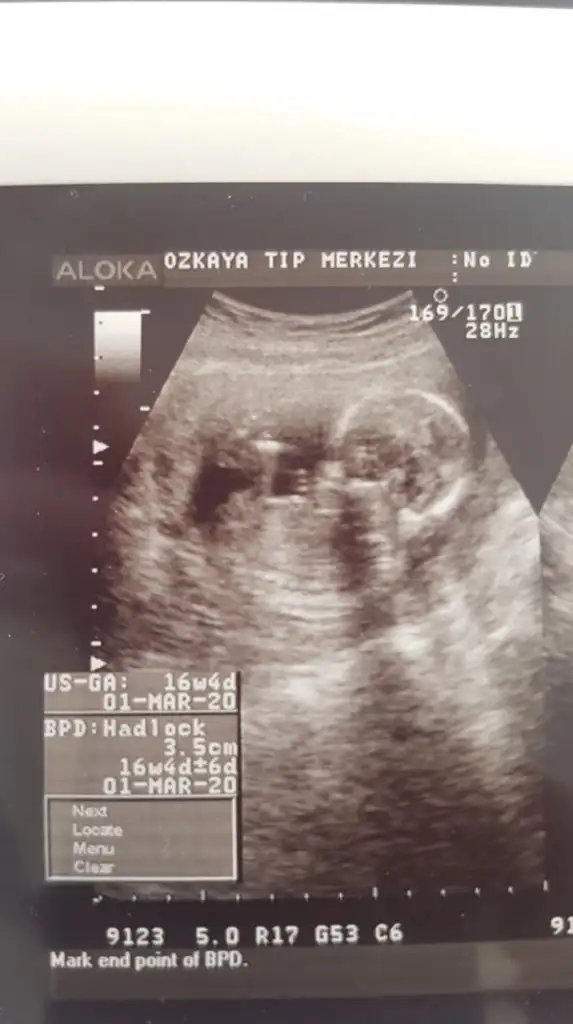

merhaba dün 2 farklı yerde ultrason çektirdik ama cinsiyetini öneremedik rica etsem usg bakıp tahmininizi söyliyebilirmisiniz 16. haftayıda geçtik hayırlısıyla teşekkkürler.

merhaba dün 2 farklı yerde ultrason çektirdik ama cinsiyetini öneremedik rica etsem usg bakıp tahmininizi söyliyebilirmisiniz 16. haftayıda geçtik hayırlısıyla teşekkkürler.Eki Görüntüle 2309422

11 yada 12 hafta olmalı nub için kafa şekli erkek gibi ama tutmayabilir siz 11 yada 12 hafta usg paylaşın